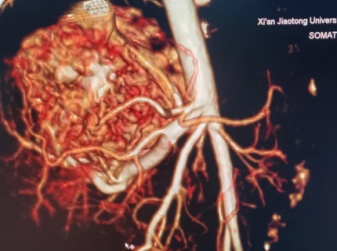

患儿妈妈怀孕期间产检发现肝脏占位,血运丰富,并随着时间的推移,肝脏占位逐渐变大,孕38+5周外院彩超提示肝脏肿块增长至7.3*4.3cm。宝宝出生后第一天即出现拒乳、呼吸困难、心率快等表现,考虑宝宝的情况为肝脏的血管瘤并有肝动-静脉瘘,引起心脏持续高动力状态,导致心功能不全,这是一种能够危急患儿生命的紧急情况,需要及早干预治疗,家属遂即慕名转至我院新生儿科。入住新生儿科后王惠萍教授紧急联系B超室乞艳华副教授完善心脏以及肝脏彩超评估患儿心功能以及瘤体大小,宝宝的肝脏占位正逐渐增大,心功能逐渐恶化,留给家属和医生的时间正在减少;小儿外科高亚教授心系患儿安危,多次查看、询问患儿情况,并根据每次复查指标,作出指示:决定使用微创介入的方式进行肝动脉栓塞术,封堵肿瘤血供。但新生儿血管纤细,动静脉瘘广泛,新生儿设备、管路、用药禁忌等诸多难题,成功的案例国内外鲜有报道,西北地区尚无类似病例报道。为了给患儿争取生存的机会,组织影像科介入组、小儿外科、麻醉手术科、医用超声科、新生儿科等院内多学科MDT团队进行了评估以及手术方案讨论, 反复论证手术的可行性,提出手术可能存在的风险以及应急策略并做好充分准备。

3月13日,在小儿外科高亚教授、郑百俊教授及郭新奎教授及多学科的积极配合下,为患儿进行了肝动脉造影术+肝动脉栓塞术。新生儿股动脉纤细,常规股动脉鞘作为入路存在术后股动脉闭塞下肢缺血风险,采用了经股动脉单纯微导管超选择性栓塞,手术难度大大增加,但避免了股动脉缺血风险。

在麻醉科(吴刚副主任,罗倩倩、陈趟医生)和新生儿科(王惠萍教授、王莉医生)的保驾护航下、超声科(何鑫医生)的精准定位置管,血管介入团队(彭玉萍教授、刘强教授、杨晓东医生)经过3小时的努力,共封堵四处肝血管瘤的主要供血动脉分支,手术过程患儿生命体征稳定,血管瘤的血流量逐渐减少,进行心功能测定显示心输出量较术前下降,效果显著,肝脏的“扫雷”行动获得阶段性的成功,在场的所有医务人员为孩子鼓掌加油!